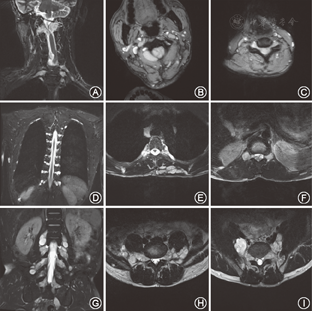

所调查的家系成员共15名,发病患者7例,均发现有肢体无力症状,MRI证实有脊椎多发的椎管内神经纤维瘤,而其他成员MRI均未发现椎管内神经纤维瘤。患者均无咖啡牛奶斑、虹膜Lisch结节、脊柱侧凸,无内脏肿块压迫出血症状,无耳鸣、听力下降,头晕,无持续性头痛、恶心、呕吐和视物不清等颅内压增高等临床表型(图1)。先证者(Ⅲ9)的MRI示左侧丘脑可见小斑片状长T1长T2信号,T2WI-FLAIR呈高信号;余双侧侧脑室旁白质内可见条状或类圆形长T1长T2信号,T2WI-FLAIR呈低信号;部分脑沟、池、室增宽。提示左侧丘脑高信号小病灶,轻度脑腔隙,轻度脑萎缩(图2)。双侧颈胸腰椎椎间孔及骶管扩大,双侧颈、胸、腰及骶神经根走行区见多发串珠状、丛状、囊状类圆形或梭形病灶,边界较清,长T1长T2信号,压脂T2像呈高信号。较大者位于颈1~2双侧椎间孔区,右侧较大,约2.5 cm×2.1 cm×1.8 cm,部分长入局部椎管内,明显压迫局部硬膜囊及脊髓。颈5~6右侧椎间孔区病灶部分长入椎管内右侧部,大小约1.3 cm×1.1 cm×1.8 cm,压迫局部硬膜囊及脊髓,向左侧移位。胸12至腰1左侧椎间孔区病灶部分长入局部椎管内,矢状位约0.9 cm×1.0 cm,局部脊髓圆锥稍受压移位。扫描区内胸腰背部皮质及部分肌肉间隙内见多发病灶,呈等T1等T2信号或长T1长T2信号,最大径约2.6 cm(图3)。颈1~2椎管外、颈5~6椎管内肿瘤切除术后病理:节细胞神经瘤(图4)。免疫组织化学:Ki67(1%+),S100(+++),神经元特异性烯醇化酶(节细胞+),Neu-N(节细胞+),Nf(节细胞+),SY(节细胞+)(图5)。